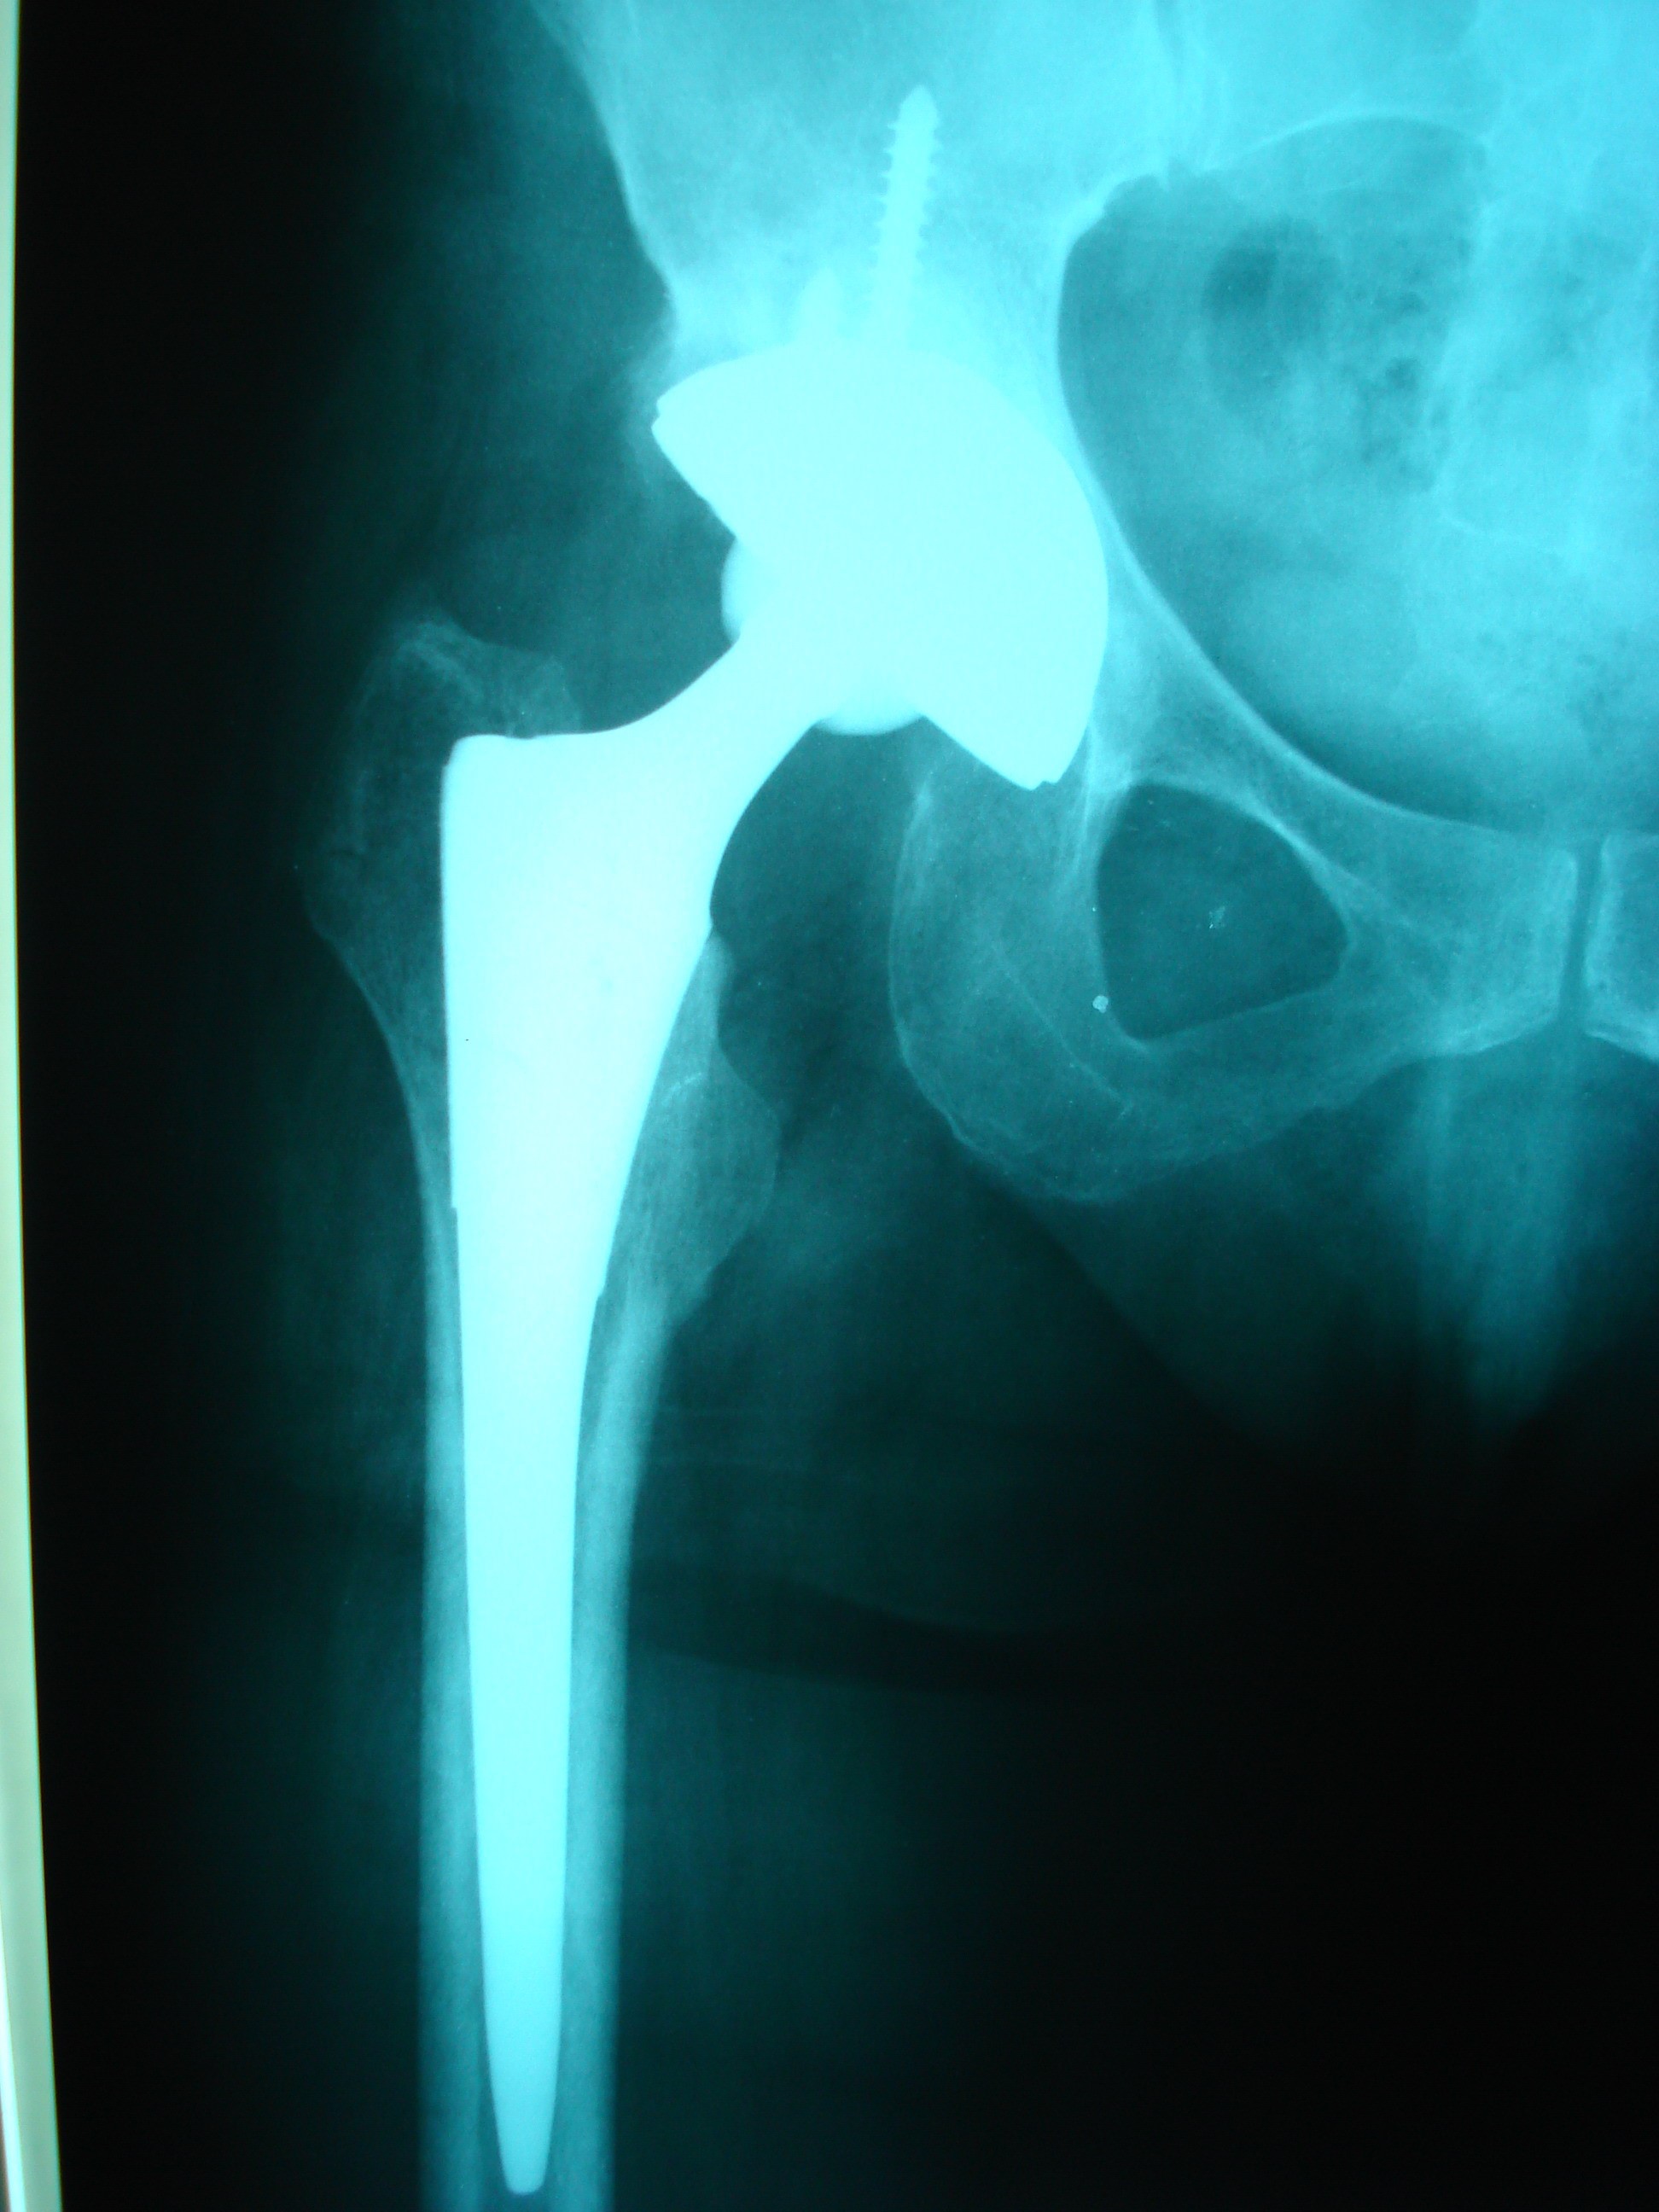

Hasta yaşlı ise, bu bölgede kırık iyileşmesi sorunlu olabildiğinden eklem protezleri uygulanarak hastaların tedavisi sağlanır. Protez uygulanan hastalar, ameliyat sonrası ameliyatlı ayağa tam yük verebilirler.

Tedavi: Hastayı yatağa bağımlılıktan bir an önce kurtarmak ve eskisi gibi yürümesini sağlamak ya da yatak içinde ağrısız bakımını sağlamak amacıyla cerrahi tedavi uygulanmalıdır.

Tedavide hedef, hastayı yatağa bağımlılıktan kurtararak ek sorunların oluşmasını engellemektir. Ameliyat olmayan hastaların ölüm riski yüksektir. Bu nedenle kalça kırıklarının güncel tedavisi ameliyattır. Ancak, kalça kırığı olan hastaların metabolik dengeleri sorunlu olduğu için azami özen gösterilmeli, her türlü hazırlık yapıldıktan sonra ( konsültasyonlar) ideal şartlarda hastalar yarı acil olarak ameliyat edilmelidir. Kalça kırığı olan hastaların yaklaşık olarak 1/3 ü ameliyat döneminde ( ameliyat öncesi-ameliyatta – ameliyat sonrası erken dönemde) kaybedilebilmektedir.